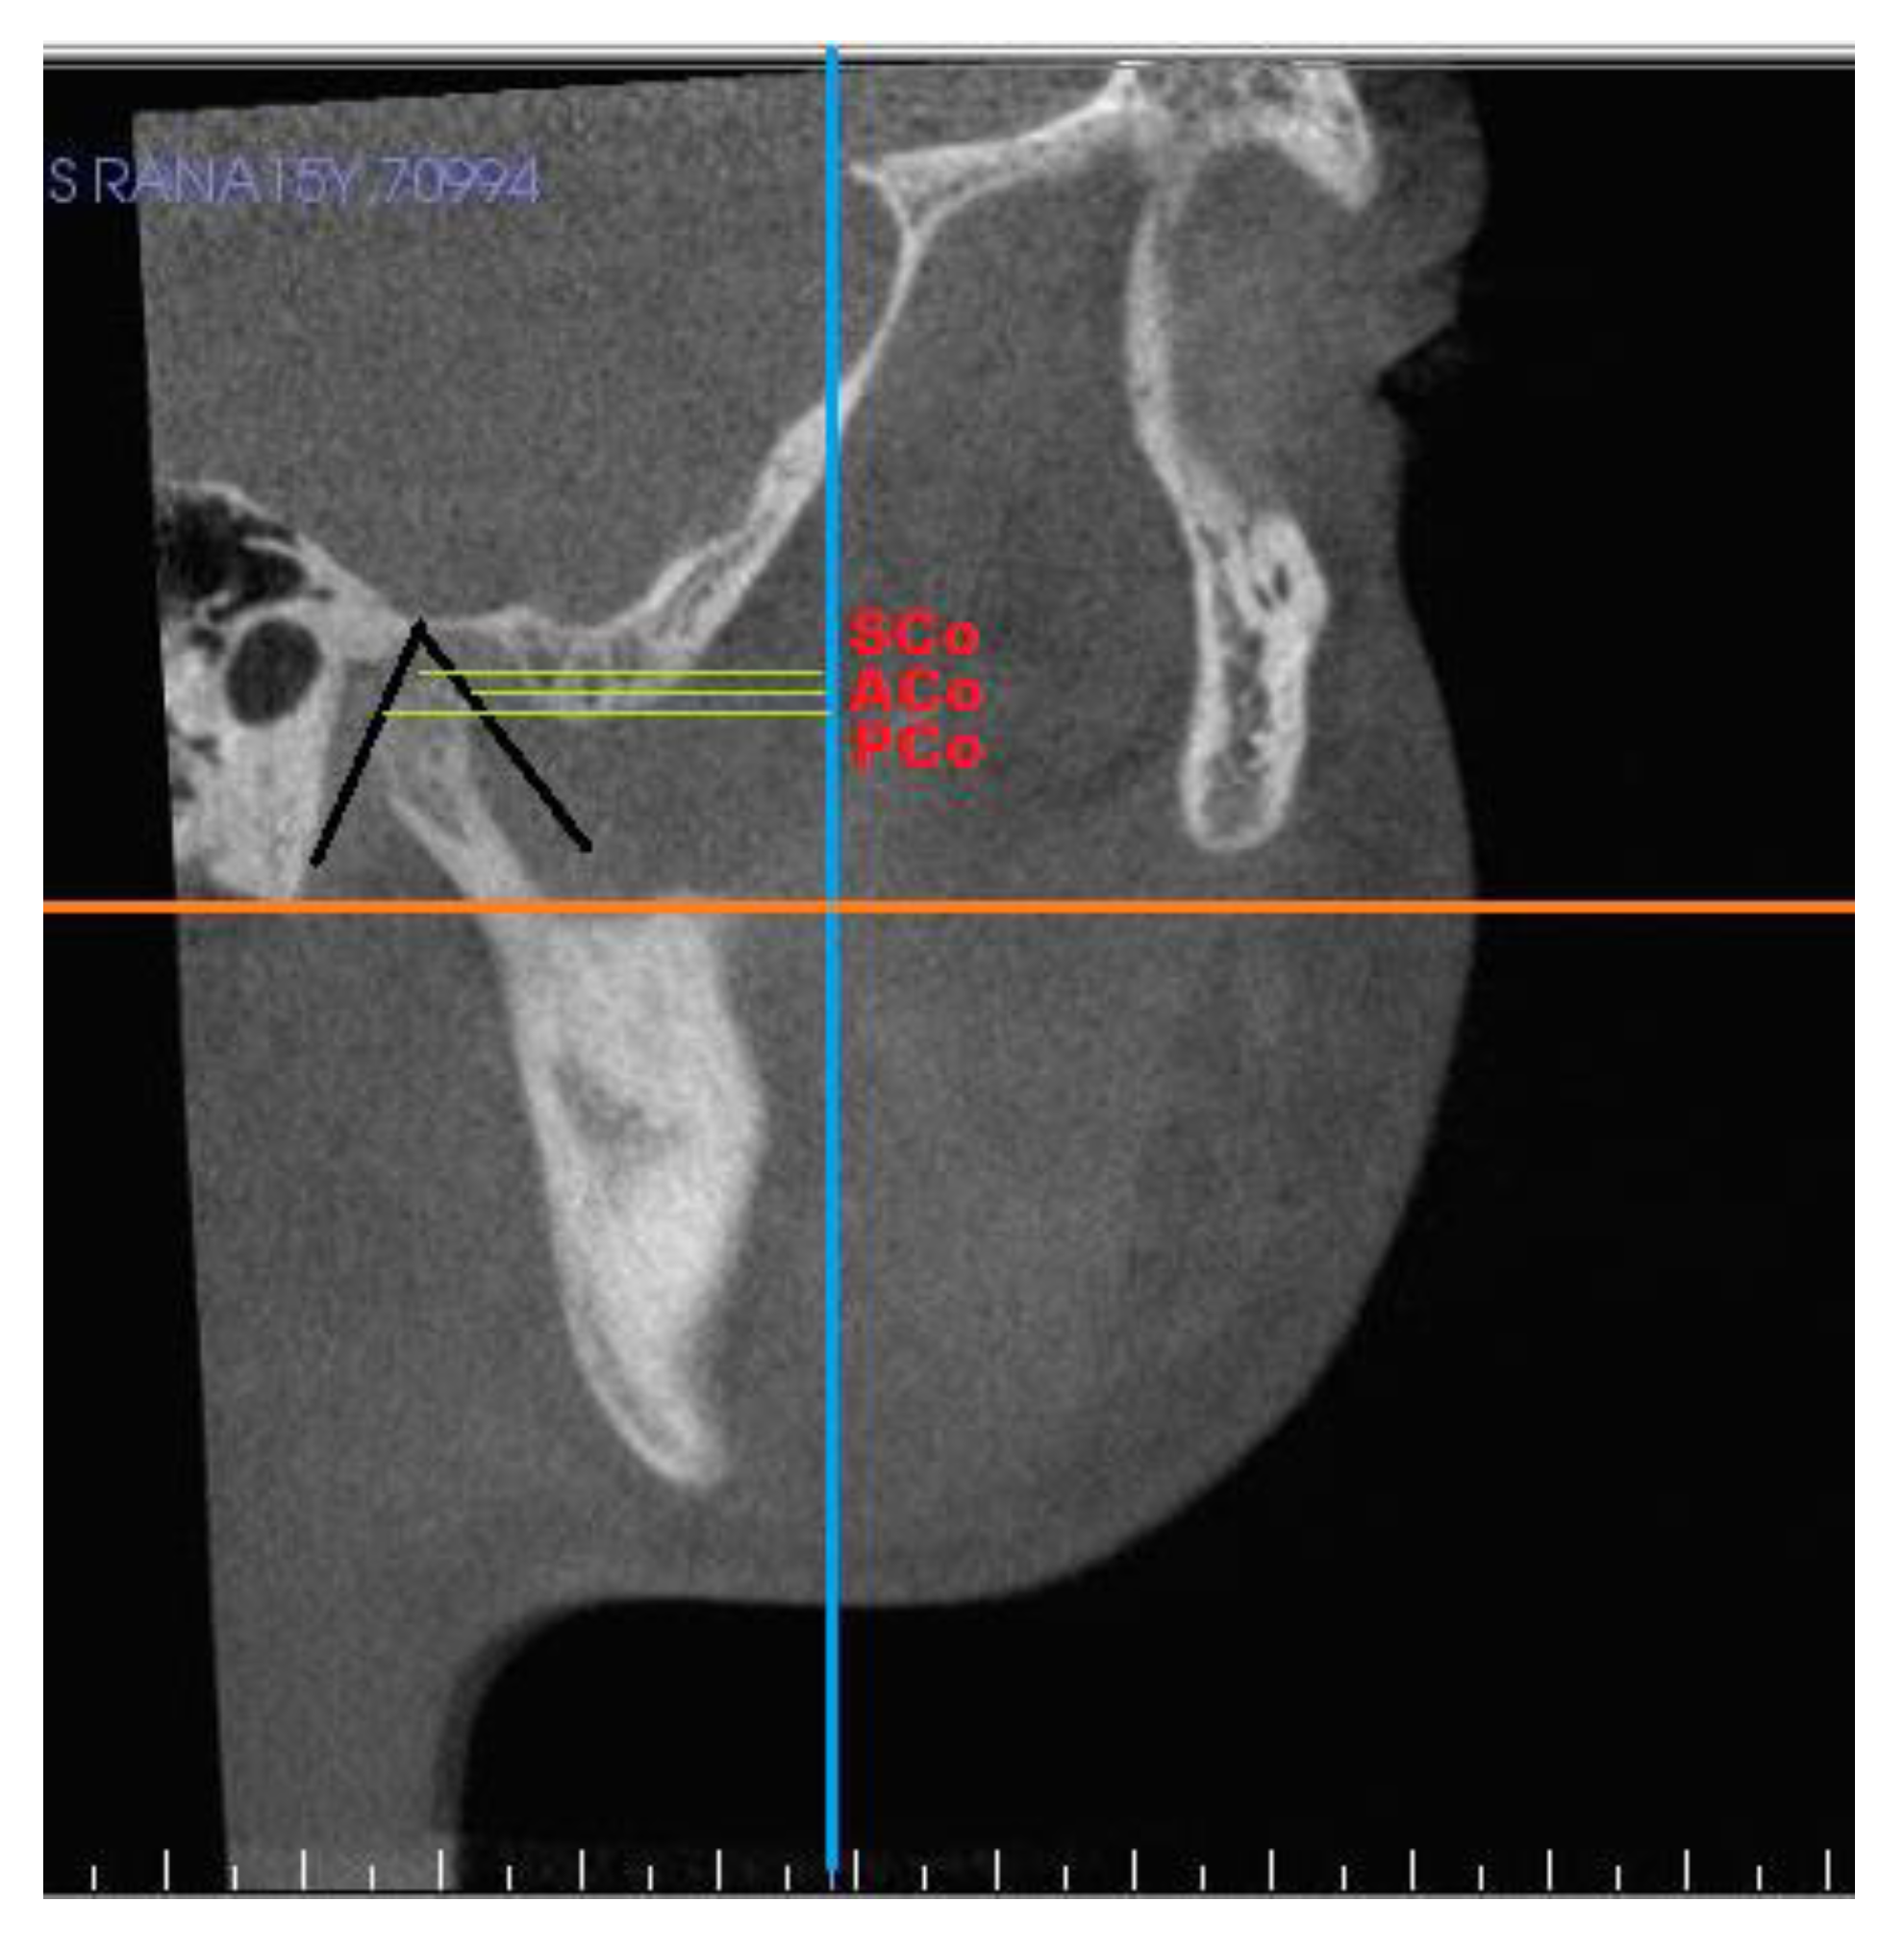

| S. No. | Measurments | Definition |

|---|---|---|

| Condyle | ||

| 1 | Superior joint space | Linear distance from superior point on condyle to highest point on glenoid fossa |

| 2 | Posterior joint space | Linear distance from posterior point on condyle to posterior surface of fossa |

| 3 | Anterior joint space | Linear distance from anterior point on condyle to a point on articular eminence |

| 4 | SCo–T vertical | Linear distance from superior point on condyle to pterygoid vertical |

| 5 | PCo–PT vertical | Linear distance from posterior point on condyle to pterygoid vertical |

| Glenoid fossa | ||

| 6 | ACo–PT vertical | Linear distance from anterior point on condyle to pterygoid vertical |

| 7 | PF 1 to PT vertical | At distance 3 mm from superior point of fossa |

| 8 | PF 2 to PT vertical | At distance 5 mm from PF1 |

| 9 | PF 3 to PT vertical | At distance 6 mm from PF2 |

| 10 | PF 4 to PT vertical | At distance 3 mm from PF3 |

| 11 | Condylar height | Distance from SCo to constructed perpendicular line. |

| 12 | Condylar volume | Volumetric analysis of each mandibular condyle after isolating it. |